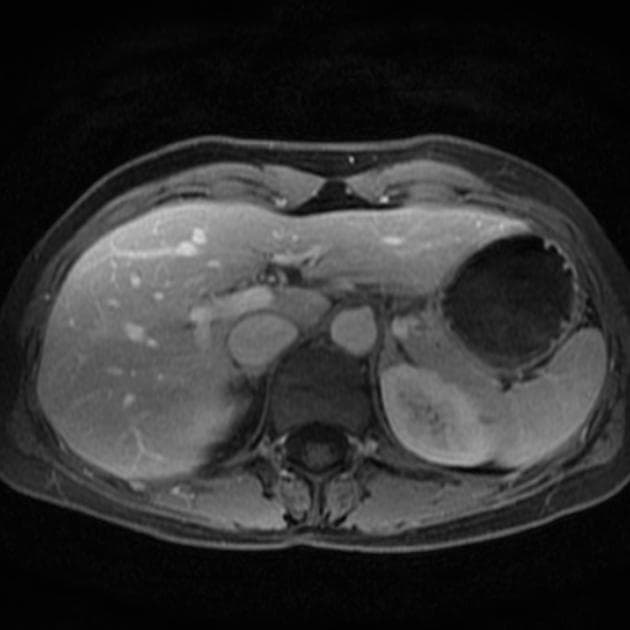

- Tổn thương dạng thùy (lobulated) kích thước 35 x 45 mm nằm ở phân đoạn V của thuỳ phải, liền kề với túi mật (gallbladder).

- Tổn thương này tăng tín hiệu (hyperintense) trên hình ảnh T2-weighted MRI.

- Trên hình ảnh cộng hưởng từ có tiêm thuốc tương phản động (dynamic contrast-enhanced imaging), thấy tăng quang dạng nốt (nodular) ở vùng ngoài viền (peripheral) ban đầu, tiếp theo là quá trình lấp đầy dần từ ngoài vào trong (slow centripetal filling).

Hình ảnh cộng hưởng từ (MRI) phù hợp điển hình với u sợi mạch gan (hepatic hemangioma).

U sợi mạch gan là khối u gan lành tính phổ biến nhất, thường được phát hiện tình cờ trên hình ảnh học. Bệnh xuất phát từ các mạch máu bất thường và gồm các khoang giãn chứa đầy máu được lót bởi tế bào nội mô. Trên cộng hưởng từ (MRI), hình ảnh điển hình bao gồm tăng tín hiệu rõ rệt trên T2 và kiểu tăng quang dạng nốt ở vùng ngoại vi trong thì động mạch, tiếp theo là quá trình lấp đầy dần từ ngoài vào trong ở các thì muộn. Dấu ấn hình ảnh này rất đặc hiệu, cho phép chẩn đoán chắc chắn không xâm lấn trong hầu hết các trường hợp. Mặc dù có thể sinh thiết, nhưng thủ thuật này tiềm ẩn nguy cơ chảy máu và thường được tránh. Điều trị mang tính bảo tồn, không cần cắt bỏ hay theo dõi định kỳ trong các trường hợp điển hình, trừ khi có nghi ngờ chẩn đoán hoặc bệnh nhân có triệu chứng.